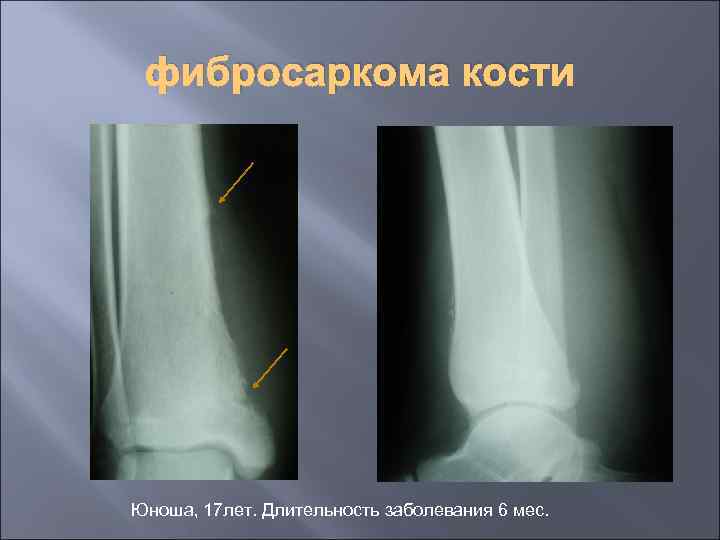

фибросаркома кости Юноша, 17 лет. Длительность заболевания 6 мес.